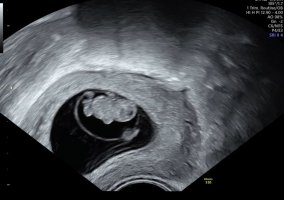

Jeg var på Ultralyd I dag. Ble flyttet fra 6+4 til 7+0.

Så en liten en med hjerteslag.

Åå då godt å høre! Ja for føler det er litt derfor jeg vil på TUL for å høre hjerteslag og se at alt står bra tilJeg var på TUL når jeg var 6+3 og fikk se hjerteblink![]()

Åååh gleder meg ikke noe mindre nå!Kjempe fin tid for første tulhar hatt mine første tul I uke 7 i tidligere svangerskap og da er det en bamsemums;

Til å ligne en bitteliten baby med armer og ben, og litt bevegelse når en kommer over 8 uker (8+3);